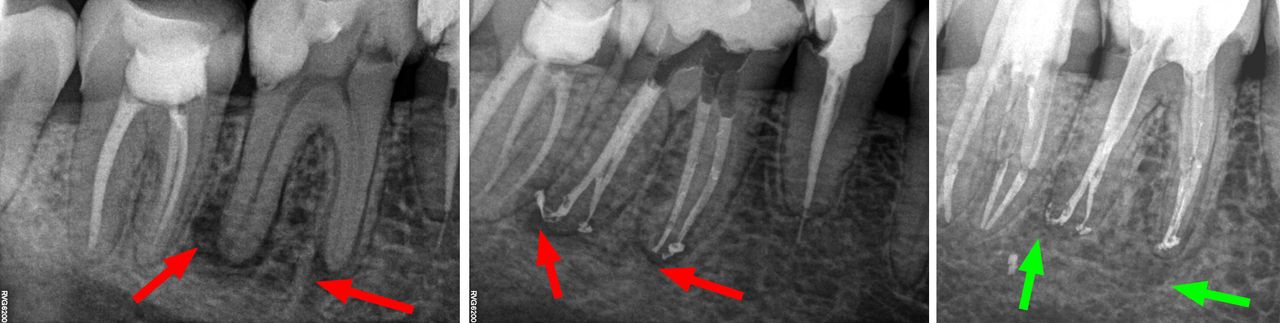

- Usuwanie złamanych narzędzi kanałowych oraz innych ciał obcych pozostawionych w kanałach korzeniowych

- Zamykanie perforacji w korzeniach zębów

- Specjalizujemy się w powtórnym leczeniu kanałowym i leczeniu powikłań co oznacza, że mamy wieloletnie doświadczenie w usuwaniu złamanych instrumentów kanałowych w szybki, bezbolesny i nieinwazyjny sposób. Dr Gończowski jest autorem specjalistycznego zestawu mikroinstrumentów (FRS®) przeznaczonych do usuwania ciał obcych z kanałów korzeniowych